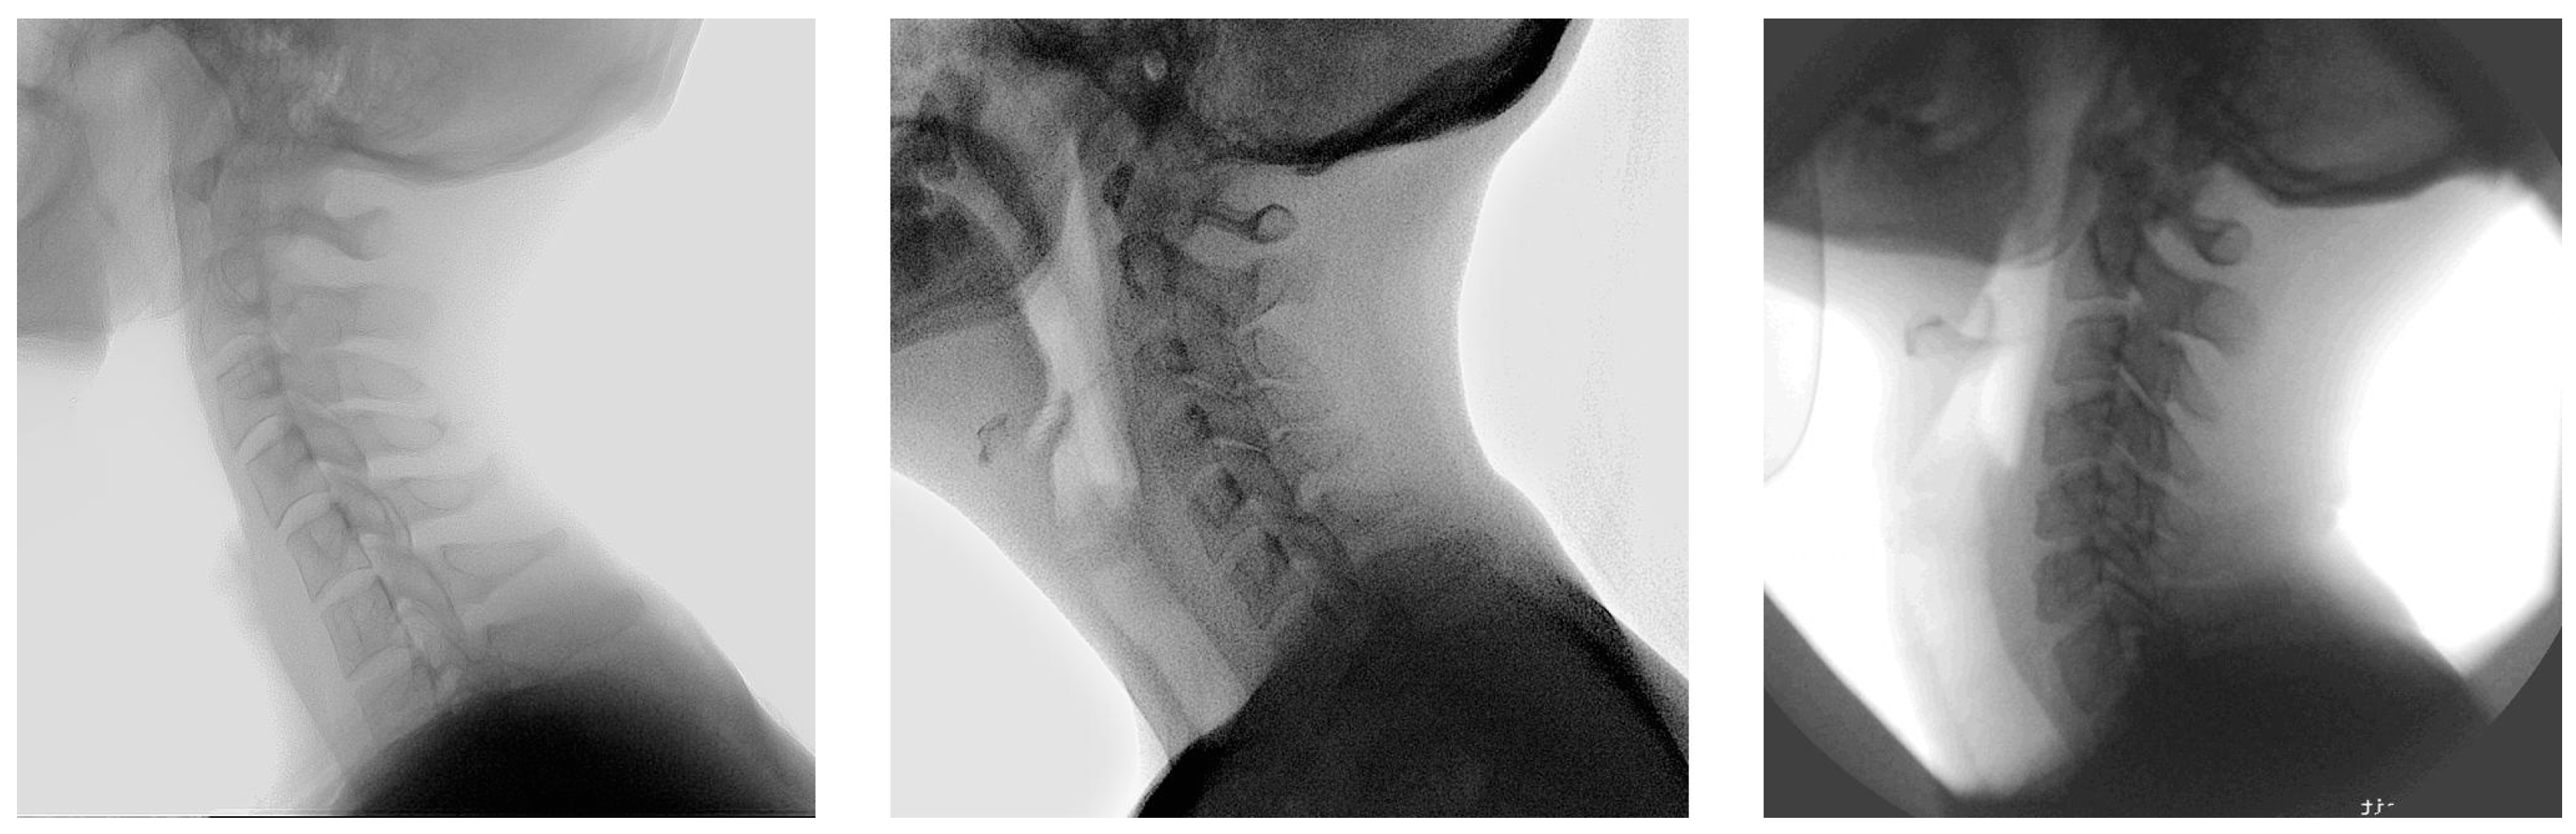

2.1. Population

2.4. Dataset